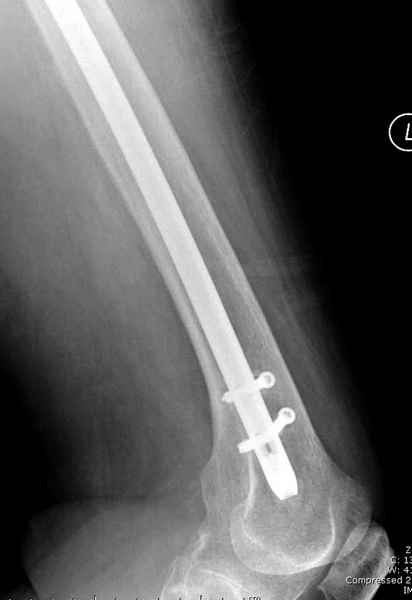

Михаил, здравствуйте. Если присмотреться - на четвертом снимке есть перелом гвоздя по отверстию.

Видимо, проблем тут две: во-1-х, центральный отломок был оставлен в варусно-сгибательной установке, во-2-х, не динамизировали вовремя.

Нижние винты хотели сломаться, но, увы, один не сломался, и тогда сломался гвоздь. Хотя и при динамизации в таком положении отломков

могло не срастись.

Не стали усложнять интрамедуллярным вариантом коррекции, легче контролировать коррекцию пластиной, поэтому сделали операцию 95 градусной Blade Plate, разогнув до 110 градусов.

Надеемся на успех, потому что до введения пластины дефект от импланта забили костной стружкой и удалось создать компрессию между отломками, максимальную для импланта (150 кило/паунд). Сделана дополнительная костная пластика и за счет измененного угла пластины устранено укорочение конечности.

Страйкер предоставил отличный инструмент - крючок для удаления длинного гвоздя. Считаем, что врачебная ошибка по установке привела к несостоятельности импланта и к ятрогенному осложнению.